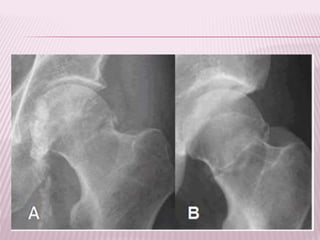

FRACTURAS TRANSCERVICALES

 Compromete la parte media del cuerpo del

cuello femoral.

FRACTURA TRANSCERVICAL